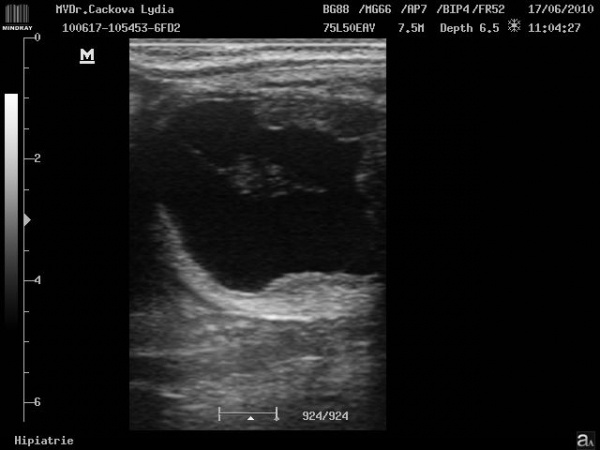

ultrasonografické vyšetření klisny

embryo kolem 21.dne

Embryo 31. den